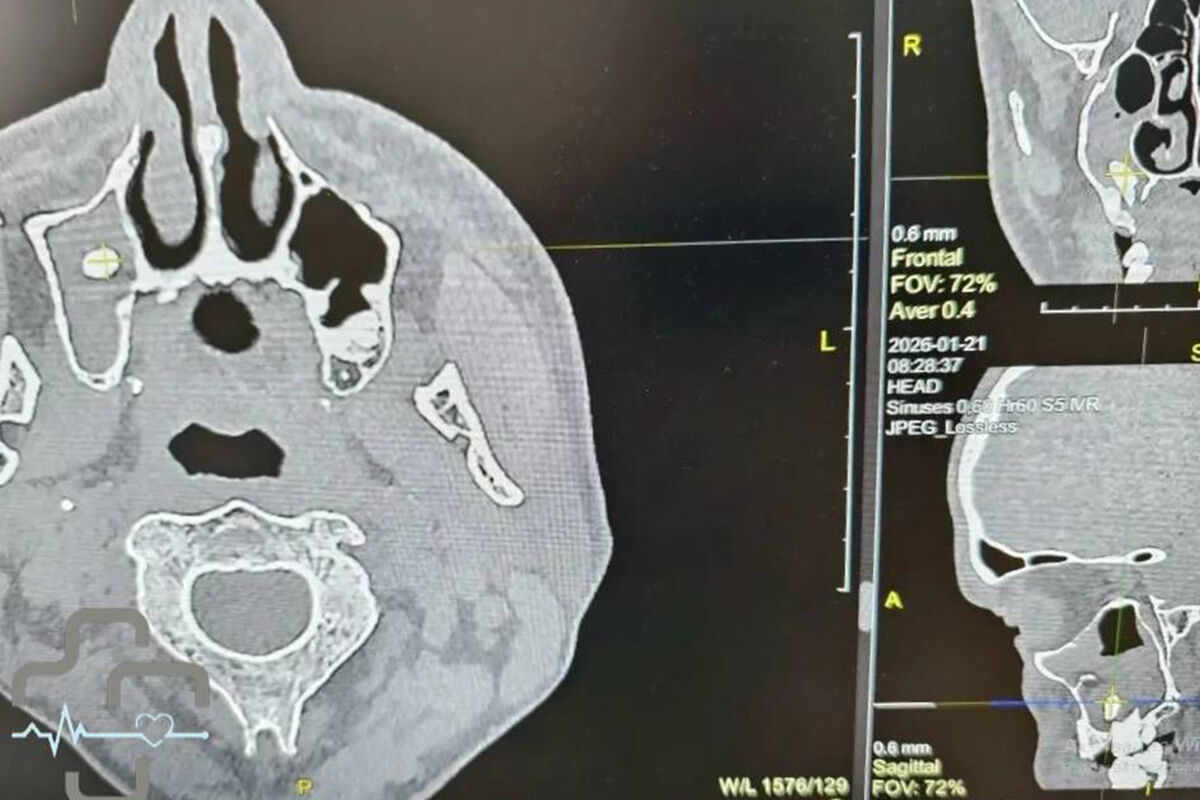

Диагностика показала, что в правой носовой пазухе мужчины находится зуб. Мужчина вспомнил, что незадолго до этого удалял зуб у стоматолога. Как пояснили врачи, во время процедуры могла нарушиться целостность костной перегородки между зубным рядом и пазухой, из-за чего зуб или его фрагмент сместились внутрь.